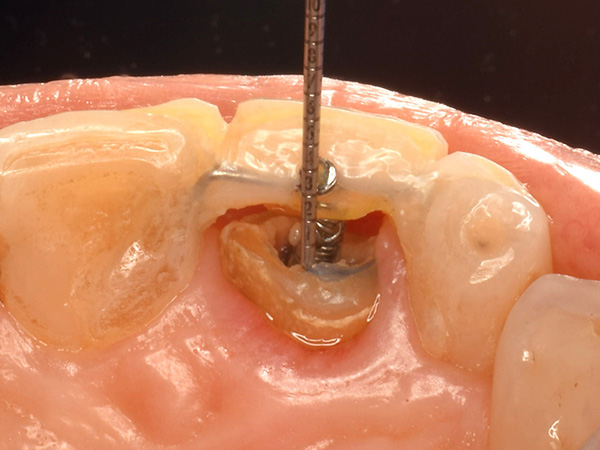

根の奥深くにひび割れが入っていたケース、その位置と深さによって、また周囲の歯質の厚みによっても矯正治療による移動距離や回転角度が異なって参ります。

『ほんとだ!回ってる、回ってる!!

単に末期的に見える歯を抜かずに救うだけでなく、見た目に美しくまたしっかり美味しいお食事が安心してとれるように。審美と機能のバランスを重視した救歯臨床を日々心掛けています。